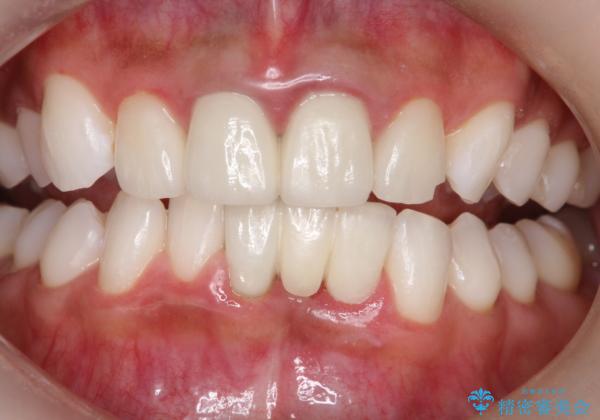

エアーフロー+オフィスホワイトニング

- 3カ月に1度、メンテナンスとしてエアーフローとオフィスホワイトニング来院されてます。

スペシャルコースのオフィスホワイトニングをされていますが、初めの1回はエクセレントコースをされてます。

現在は白さをキープする為、スペシャルかスタンダードコースにしています。

エアーフロー後のオフィスホワイトニング

エアーフロー後のホワイトニングは、バイオフィルムやぬめりがなく、ホワイトニング剤が吸収しやすく、セットで行うことをおすすめします。